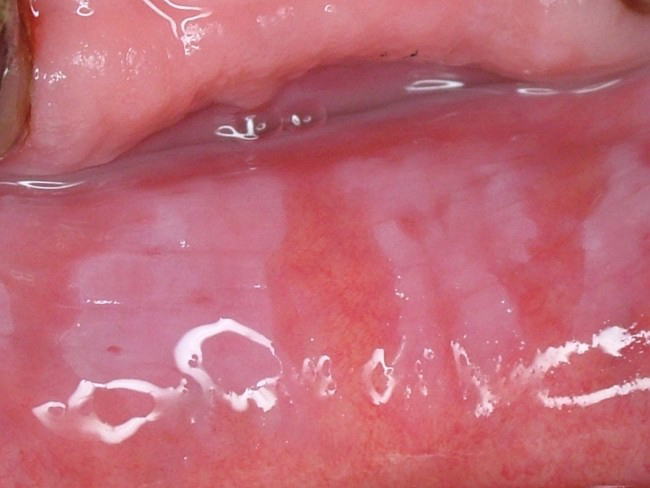

■ 白板症(ロイコプラキア) ■

頬粘膜をはじめ口唇、舌、歯肉、口腔底粘膜などに発現する”摩擦によって除去できない”白斑病変。下の写真は口唇に発現した白板症(同一写真)です。口腔粘膜疾患としては比較的頻度が高く、単発で生じることも、また写真のように広範囲に生じることもあります。表面は粗いもの、丘陵上のもの、乳頭状のもの、また境界が限局性のもの、びまん性のものなど様々な病態を示します。状態によっては前癌病変としての性格を持つものもあります。

疼痛などの自覚症状は少ないのが普通です。

治療は原因除去(不適合な補綴物の刺激によって生じたものなど)、切除、レーザー照射などがありますが、原因や病態によって多様です。

鑑別診断を要するものとしては、扁平苔癬やカンジダ症などがあります。